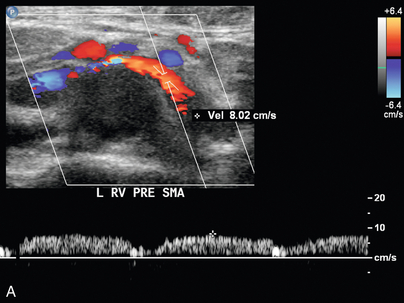

Синдром Щелкунчика

Феномен «щелкунчика» возникает в результате сдавления левой почечной вены между верхней брыжеечной артерией и аортой и может привести к гипертензии левой почечной вены, гематурии и образованию варикозно расширенных вен. Важно помнить, что у некоторых здоровых людей при КТ, МРТ или УЗИ можно обнаружить расширенную левую почечную вену. Следовательно, следует применять другие критерии, в том числе высокий коэффициент доплеровской скорости ( рис. 9-23 ) и высокий коэффициент диаметра вен, как описано в недавней литературе. Из-за сложности потенциального хирургического вмешательства может потребоваться измерение градиента давления между НПВ и левой почечной веной в качестве подтверждения до того, как будет диагностирована клинически значимая компрессия почечной вены. Визуализация крови из устья мочеточника при ретроградной уретероскопии также может быть полезной. Цветная допплерография может обеспечить неинвазивное подтверждение компрессии почечных вен с соотношением пиковых скоростей более 5:1, когда обнаружены коллатеральные вены. На КТ может наблюдаться резкое изменение калибра вен, когда вена пересекает СМА, обычно с «клювовидным» видом.

РИСУНОК 9-23 Щелкунчик с почечной веной. У пациента с необъяснимой гематурией спектральная допплерография преаортальной левой почечной вены (А) демонстрирует нормальный низкоскоростной поток, 8 см/с. (B) Когда вена пересекает аорту и SMA (допплеровские ворота), наблюдается видимое сужение с повышенной пиковой систолической скоростью, 103 см/с.